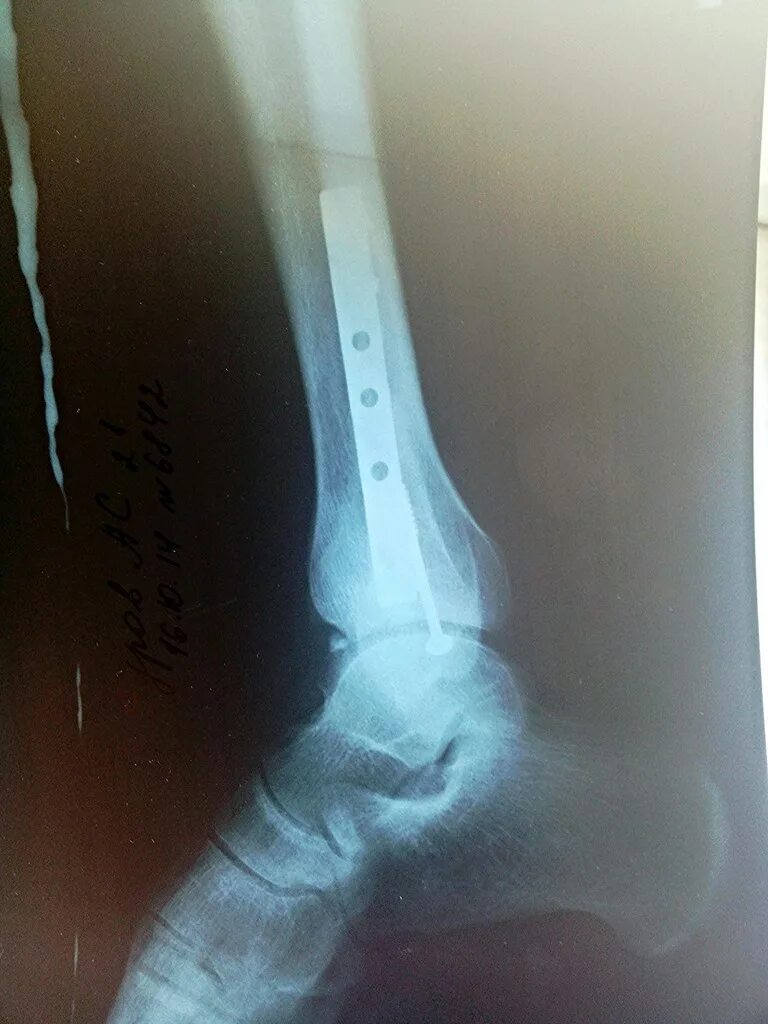

Сколько срастается ребро при переломе